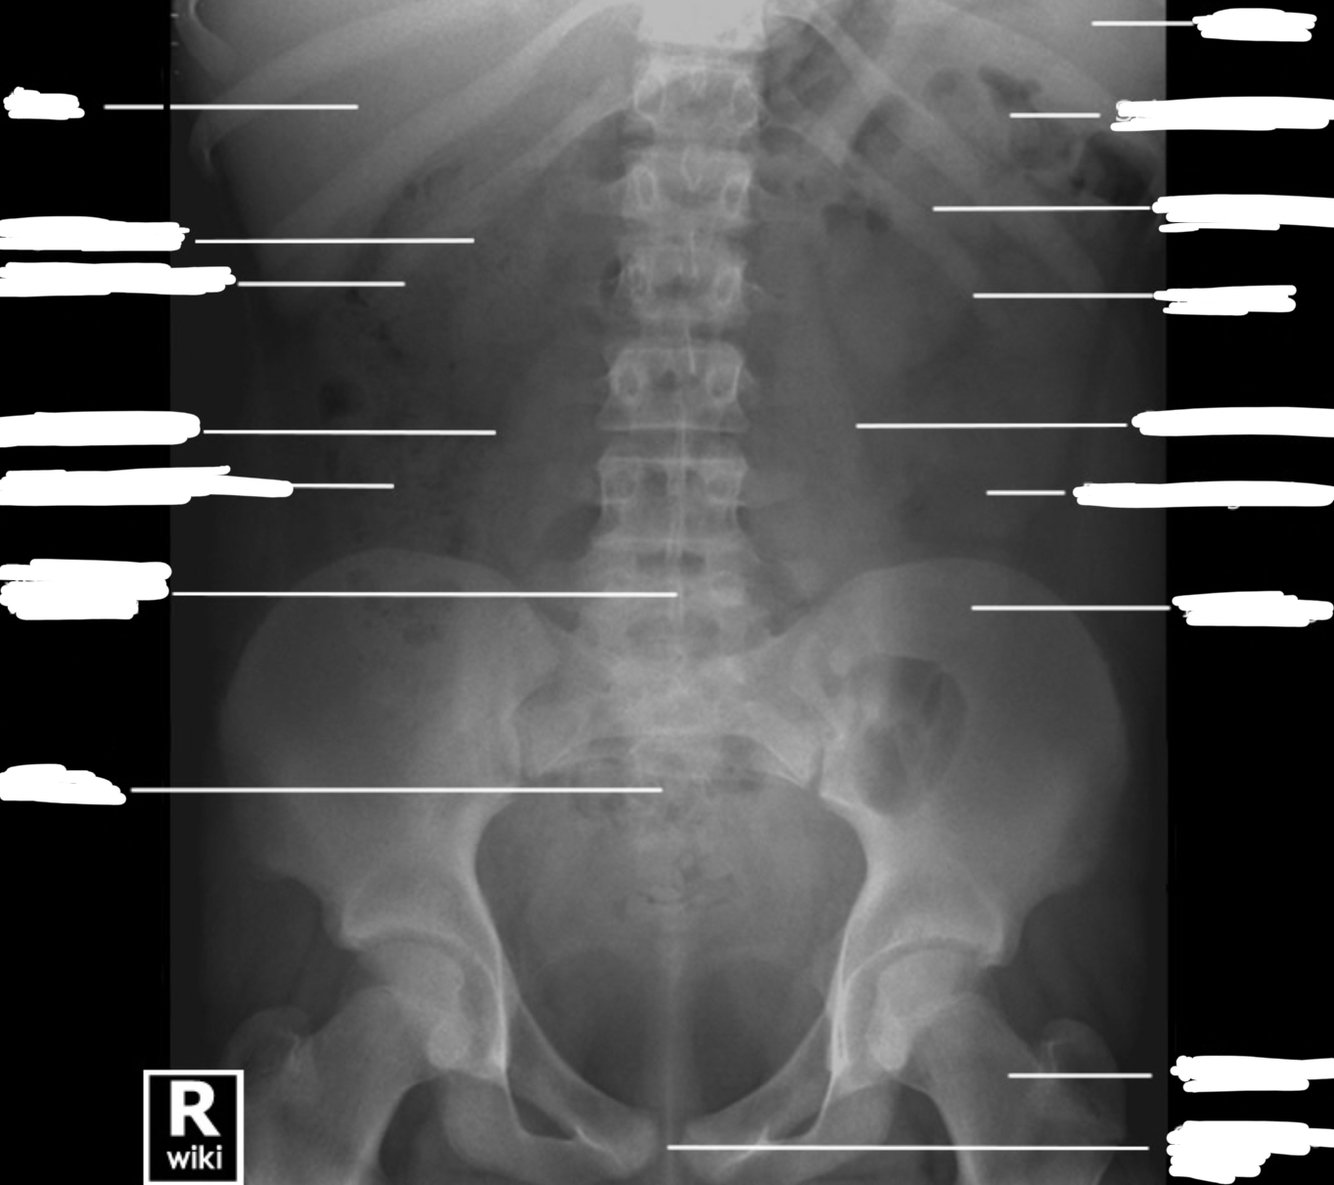

Label the viscera on the abdominal x-ray.